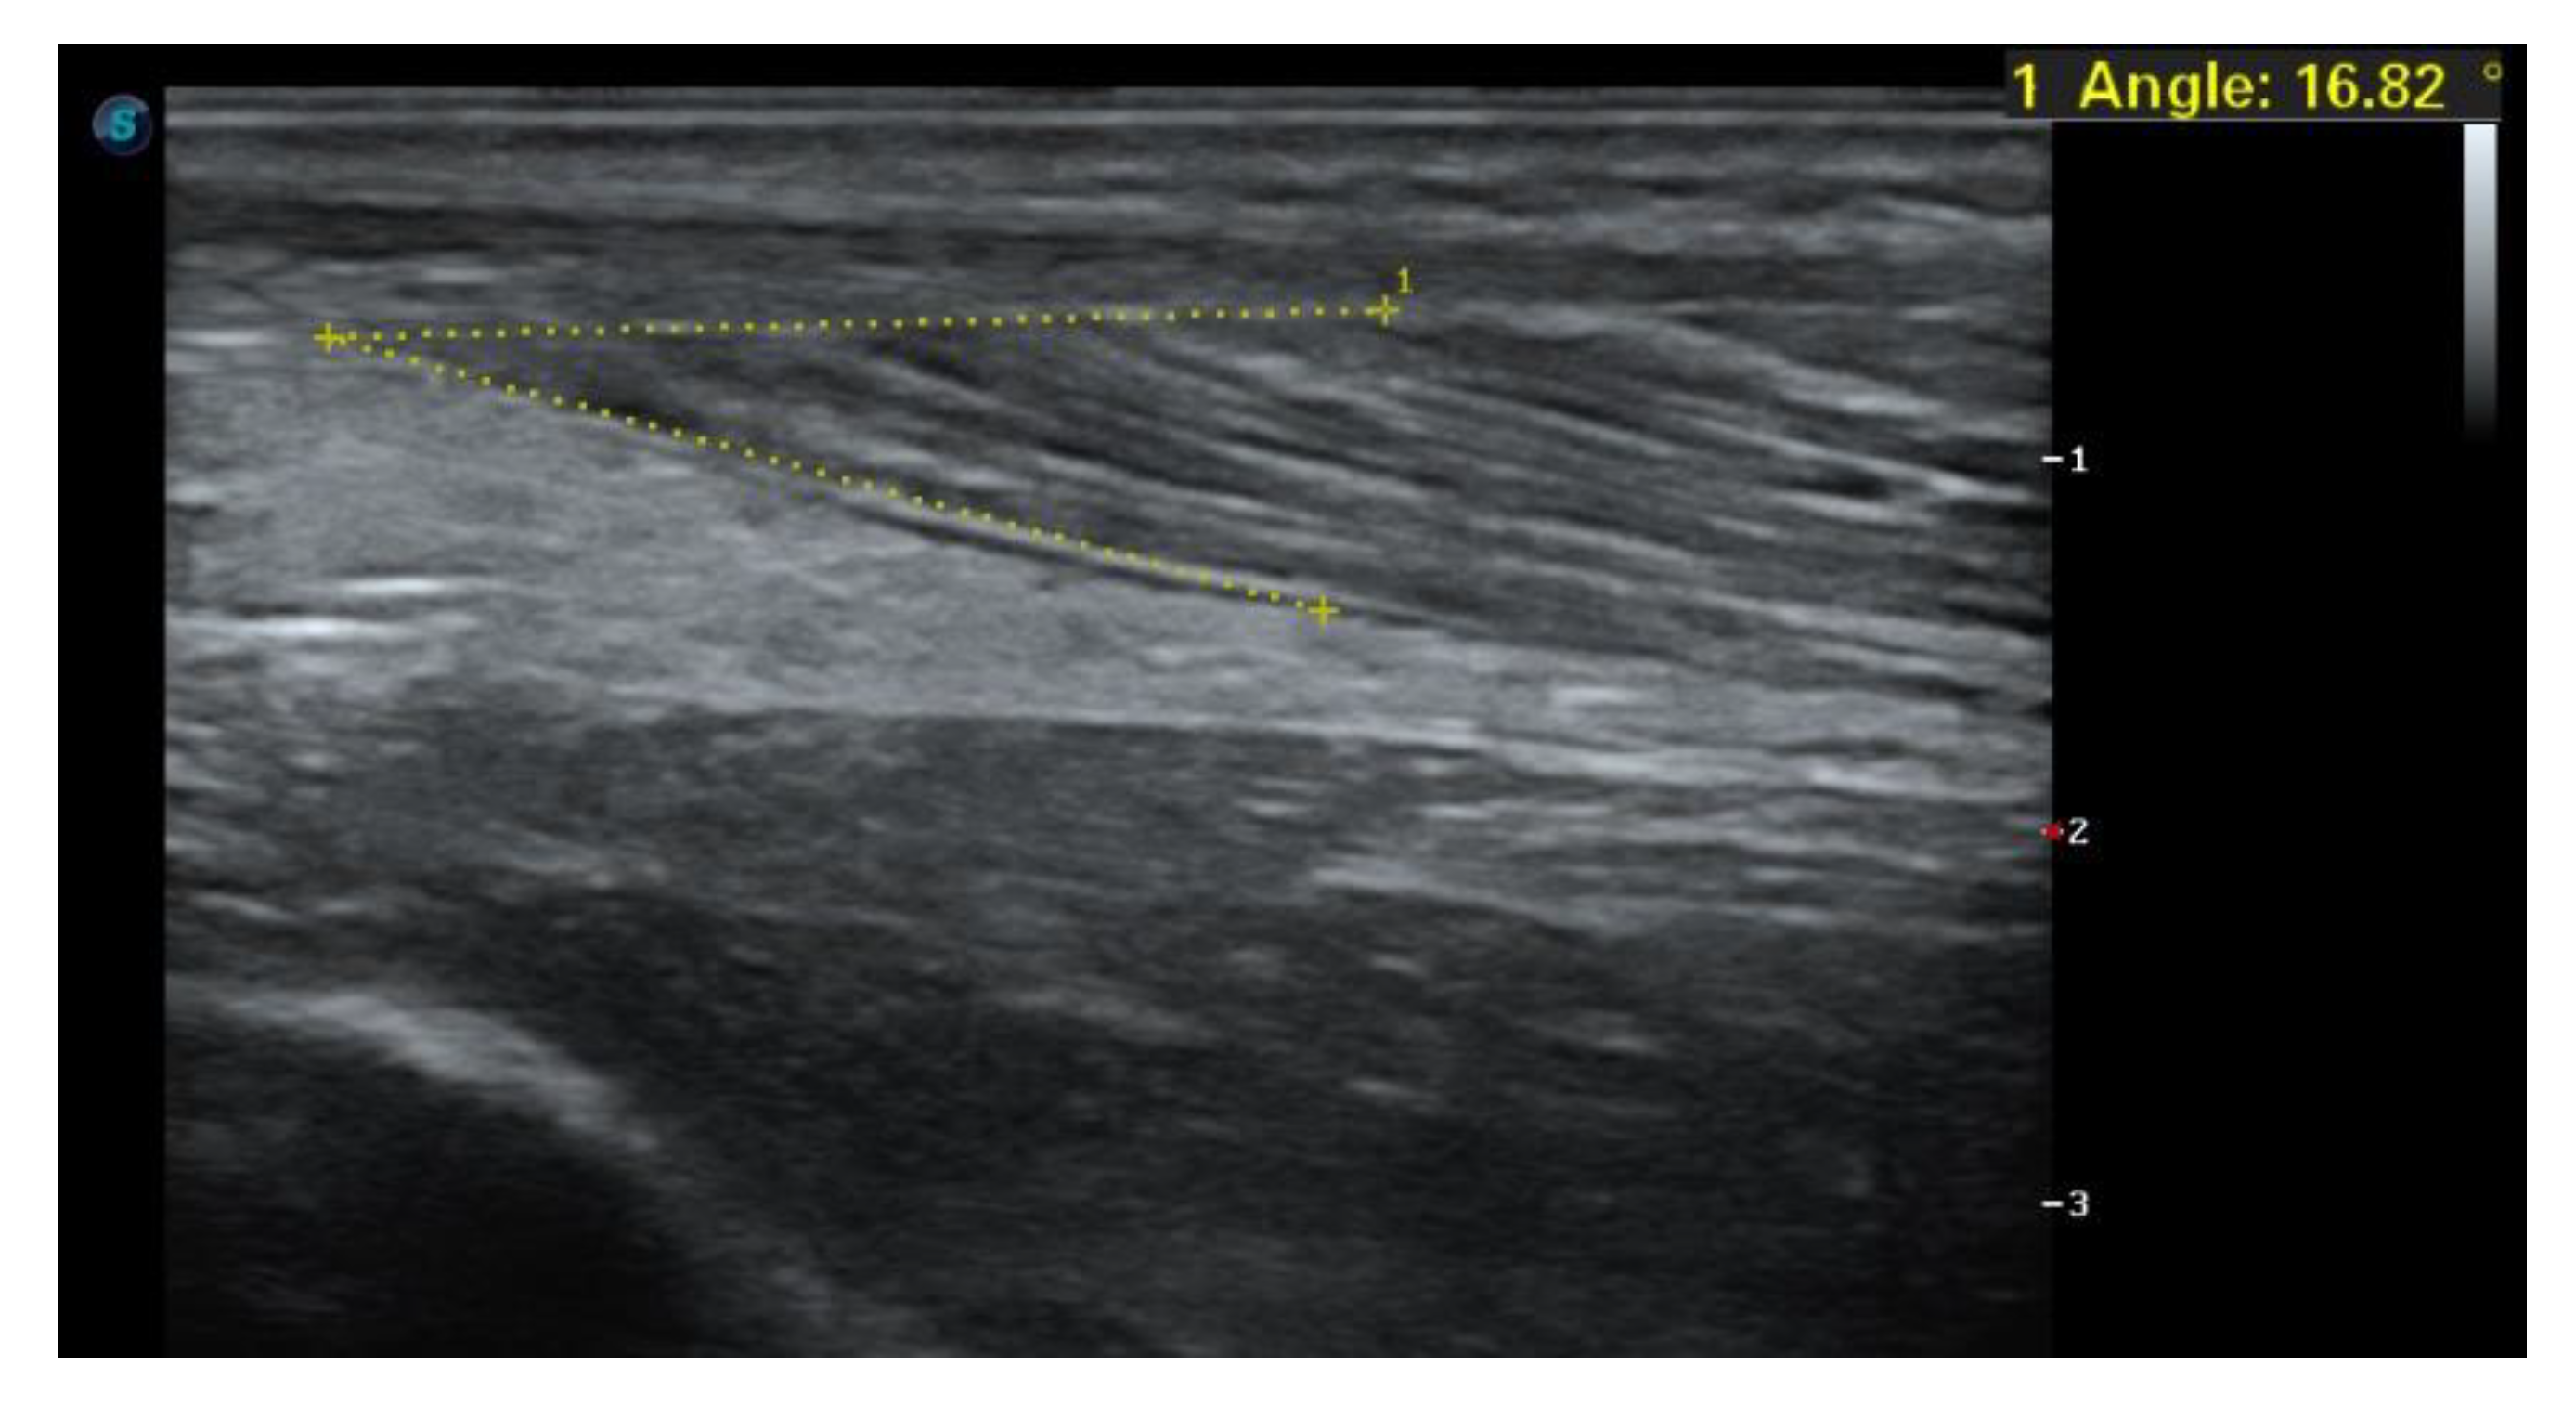

1.4. Case Report

1.5. Imaging Tests